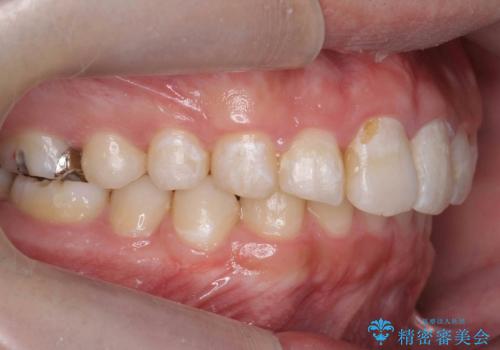

出っ歯が気になる 歯をぬかずに治療

- 前歯が出ているのを気にして来院。

左のかみ合わせが1本分ずれていましたが、機能的には問題ないのでそのまま変えずに治療しています。

ずれている分を、上の歯を1本抜くか(ワイヤー矯正になります)、右上の奥歯を1本分後ろに送るか、そのまま前歯を並べるのかを選んでいただきました。

右のかみ合わせをそのままに、最小限の動かし方で見た目を改善しました。